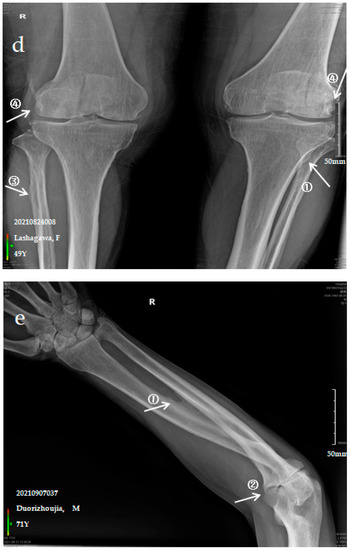

Figure 1.

X-ray imaging of SF patients. The anteroposterior actinogram of the upper limb (a) and both lower limbs (b) of patient with mild SF, the anteroposterior actinogram of the upper limb (c) and both lower limbs (d) of patient with moderate SF, the anteroposterior actinogram of the upper limb (e) and both lower limbs (f) of patient with severe SF. ①: ossification of interosseous membrane; ②: degeneration of the elbow joint; ③: Ossification shadow; ④: Ossification of knee joint capsule; ⑤: ossification of soleus tendon.

The patient is a 49-year-old female with pain in the limbs, neck and waist and limited ability to exercise with a variable impact on labour participation. The anteroposterior actinogram of the upper limb (Figure 1c) shows ossification of the interosseous membrane of the radius and ulna, with a fin-like appearance, degeneration of the elbow joint, ossification of the pronator teres muscle and bony protrusions on the inner side of the ulna. The anteroposterior actinogram of both lower limbs (Figure 1d) shows ossification of the tibiofibular interosseous membrane, a lacelike bony protrusion shadow at the tibial and fibular interosseous membrane, ossification of the long peroneal muscle, knee joint capsule and tibial collateral ligament.

The patient is a 71-year-old male with severe bone and joint pain, limited activity and no ability to work. The anteroposterior actinogram of the upper limb (Figure 1e) shows obvious ossification of the interosseous membrane of the ulna and radius, forming a large fin-like ossification near the ulna and radius. The pronator teres muscle tendon shows obvious ossification, and a stalactite ossification shadow can be seen in the radial head. There is obvious degeneration of the elbow joint. The anteroposterior actinogram of both lower limbs (Figure 1f) shows ossification of the tibiofibular interosseous membrane, with a colliculus appearance. The peroneus longus tendons show obvious ossification, as do the soleus tendon, knee joint capsule and tibial collateral ligament.

Ossification of the interosseous membrane has a high incidence and specificity in SF and is one of the important diagnostic signs of SF. Ossification of the interosseous membrane was more obvious in patients with severe SF than in those with mild or moderate SF.